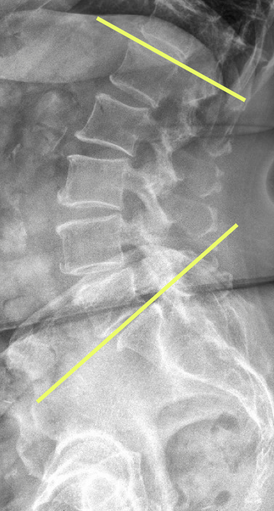

On a lateral lumbar X-ray, lumbar lordosis is typically measured by drawing lines along the superior endplates of L1 and S1, then erecting perpendiculars to each; the angle formed at their intersection is recorded as the lumbar lordosis angle.

Normal range: ~40°–60°

< 40°: Hypolordosis (can indicate flat back or postural imbalance)

> 60°: Hyperlordosis (seen in conditions like spondylolisthesis or postural compensations)